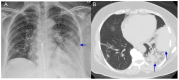

Coccidioidomycosis is a disease caused by soil fungi of the genus Coccidioides, divided genetically into Coccidioides immitis (California isolates) and Coccidioides posadasii (isolates outside California). Coccidioidomycosis is transmitted through the inhalation of fungal spores, arthroconidia, which can cause disease in susceptible mammalian hosts, including humans. Coccidioidomycosis is endemic to the western part of the United States of America, including the central valley of California, Arizona, New Mexico, and parts of western Texas. Cases have been reported in other regions in different states, and endemic pockets are present in these states. The incidence of reported cases of coccidioidomycosis has notably increased since it became reportable in 1995. Clinically, the infection ranges from asymptomatic to fatal disease due to pneumonia or disseminated states. The recognition of coccidioidomycosis can be challenging, as it frequently mimics bacterial community-acquired pneumonia. The diagnosis of coccidioidomycosis is frequently dependent on serologic testing, the results of which can take several days or longer to obtain. Coccidioidomycosis continues to present challenges for clinicians, and suspected cases can be easily missed. The challenges of coccidioidomycosis disease, from presentation to diagnosis to treatment, remain a hurdle for clinicians, and further research is needed to address these challenges.

Keywords: coccidioidomycosis; lung mass; pulmonary nodules; pyopneumothorax; valley fever.